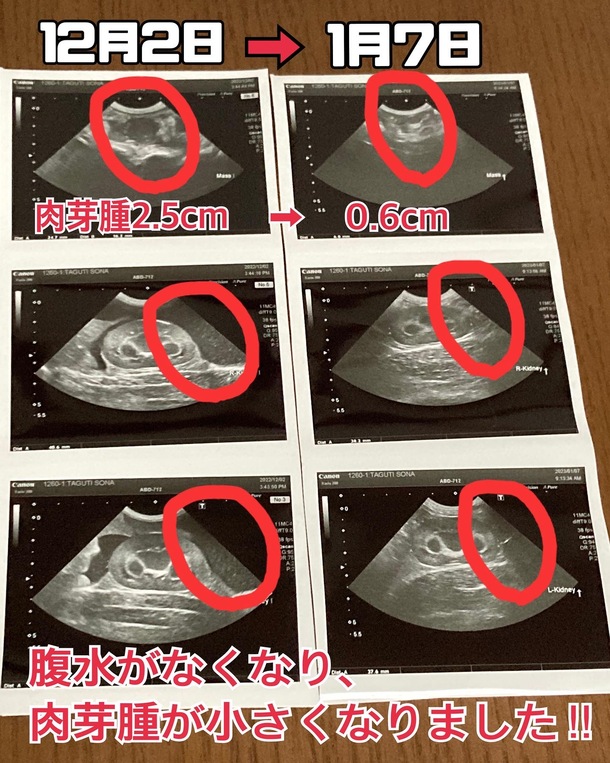

1月7日エコー結果比較

FIP発覚後の12月2日と今日のエコーを比較しています!

前回で完全に腹水がなくなったのですが、

今回肉芽腫がより小さくなりました🙌🏻🙌🏻

2.5cm→0.6cmになり、もう大きいとは言えないサイズになったと医師に言われました🥲✨

肉芽腫は無くなるわけではないので、悪性化しないように願い、定期的に検査をして様子を見ていきます‼️

お腹の中のことなので私たちに分かることではないですが、目で見える形で変化が分かるとより安心できます😂💕